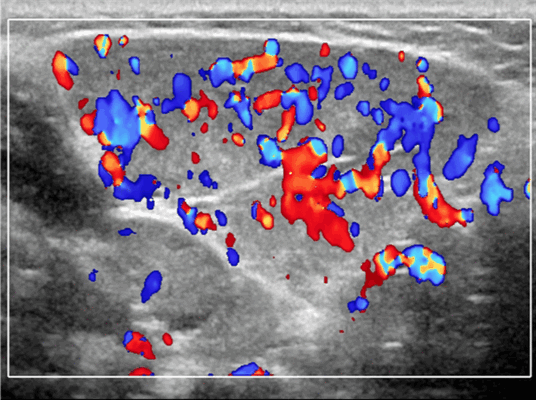

Импульсный допплер. Лоцируются артериальные и венозные волны. Средняя пиковая скорость венозной крови не повышена (повышена при истинной артериовенозной мальформации). Индекс резистентности зависит от фазы, увеличивается при лечении пропранололом (0,4-0,8)

Энергетический допплер. Отмеченный доплеровский сигнал потока на всем протяжении пораженных сосудов